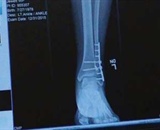

At the 2015 Turkey Meet at Skydive City Zephyrhills in Florida, my canopy collapsed at 20 feet as I was coming in on final. I broke the fibula at my left ankle and dislocated and fractured my tibia. The abrupt plunge also caused intense fear and anxiety about skydiving. Mechanical turbulence caused the accident: I landed close to the hangar and the wind rolling over it and into the landing area collapsed my parachute.

On the second jump, I felt a sudden bump and a significant drop at around 900 feet. All I wanted to do then was land and check the wind conditions. As I came around to final, I noticed I was not traveling forward much. I was getting ready to pull my toggles down to flare when I dropped straight down and landed flat on my feet. My left foot landed on a patch of overgrown grass and I rolled hard on my ankle. The snap, crackle and pop told me I had broken bones. The experience was surreal.